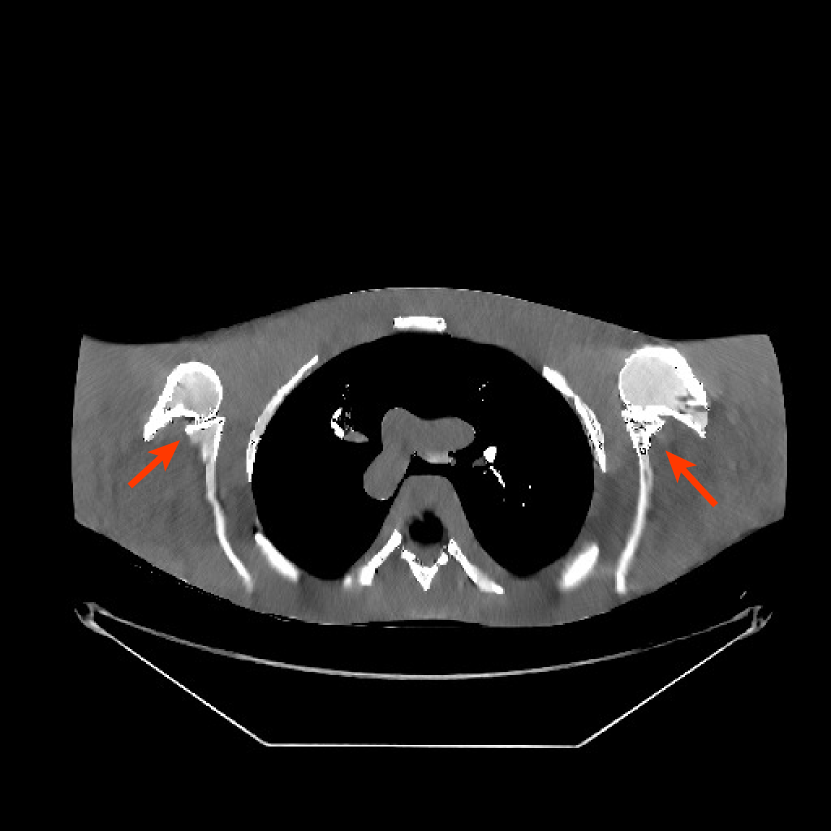

We obtained from GE a 2D fan-beam raw (pre-log) scan of a shoulder phantom, which included the beam-hardening effect. The provided with 1 second scan can be viewed as a standard-dose scan and all the raw measurements are positive. Based on this standard-dose scan, we simulated an ultra low-dose scan as shown in (15) with , and added Poisson and Gaussian noise () to the measurements. The simulated measurements have about non-positive values. The sinograms were of size , and reconstructed images were of size with mm.

For PWLS-ULTRA and SPULTRA, we pre-learned a union of five square transforms using overlapping image patches with stride from five XCAT phantom slices [38]. Here, we also compared SPULTRA with a recent deep-learning based low-dose CT denoising framework “WavResNet” combined with an RNN architecture[46]. The iterative RNN version of WavResNet was pre-trained based on the 2016 Low-Dose CT Grand Challenge data set [46]. During reconstruction, WavResNet, PWLS-ULTRA, and SPULTRA were initialized with the image reconstructed by PWLS-EP with . The parameters for both PWLS-ULTRA and SPULTRA were set as . These values worked well in our experiment. In the supplement, we discuss in detail the parameter selection procedure of for both PWLS-ULTRA and SPULTRA. Parameters for testing WavResNet were set according to [46], and the pixel values of the input to WavResNet were converted to match the network required scalings. Since the WavResNet was trained with images reconstructed with the filtered backprojection (FBP) method [46], we also tested on this shoulder phantom that initialized WavResNet with an FBP reconstructed image. Although initializing WavResNet with an FBP reconstructed image better matches the trained model than the PWLS-EP reconstructed image does, the latter still provided better results. We included in the supplement the denoised image initialized with the FBP reconstruction.

Fig. 10 shows the reconstructions for the scan (reference image) along with the reconstructions for the simulated ultra low-dose scan obtained with PWLS-EP, WavResNet, PWLS-ULTRA, and SPULTRA. Visually, WavResNet fails to reconstruct the image but improves over the initial PWLS-EP reconstruction, while PWLS-ULTRA and SPULTRA provide better image quality. This indicates that the ULTRA-based methods may have a better generalization property than WavResNet, since they learn more fundamental features of CT images (also see [38]). We selected three smooth ROIs, where the pixel values are approximately constant. Tab. V(b) shows the mean and the standard deviation of pixel values for these ROIs for various methods and the standard-dose reference. Since the iterative RNN version of WavResNet only has small improvements over PWLS-EP, the pixel values do not change much compared with PWLS-EP. PWLS-ULTRA however reduces the bias in the central region of the image (ROI 2), but fails to correct the bias in the regions near the bones (ROI 1 and ROI 3). SPULTRA reduces the bias in the central region of the image, and also significantly corrects the bias near the bone regions. The standard deviations of the ROIs reconstructed by SPULTRA are comparable to those reconstructed by PWLS-ULTRA, and are close to those of the reference ROIs. Additionally, SPULTRA reconstructs the bone (indicated by the magenta arrow in the last two subfigures of Fig. 10) better than PWLS-ULTRA.